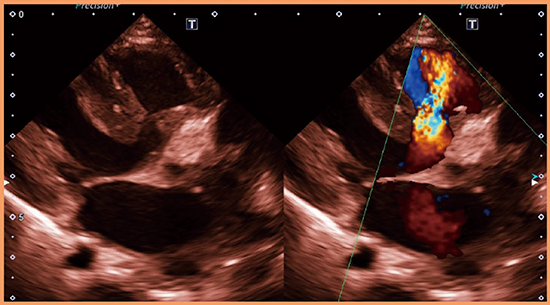

SHDに対する支援アプリケーションとしては,僧帽弁解析ソフトウエア“Mitral Valve Analysis(MVA)”および大動脈弁解析ソフトウエア“Aortic Valve Analysis(AVA)”が搭載されている。

MVAでは,1心周期の動画解析が可能となっており,マイトラクリップ前後の弁輪部や弁口面積などの計測を可能としている(図10 a)。

AVAは,TAVIに特化した支援アプリケーションである。大動脈弁が観察可能な3D画像上で軸の設定を行い,ワンクリックで自動的にトレースラインが決定される。装置上で簡単に解析が可能なため,TAVIの術場においても利用できる(図10 b)。

さらに,生体弁の種類・サイズを選択すると弁輪径や弁輪面積の目安を示す機能も実装されており,実際の計測値と比較することが可能である。

図10 MVAによる解析結果(a)とAVAによる解析結果(b)

(画像ご提供:聖マリアンナ医科大学・出雲昌樹先生)